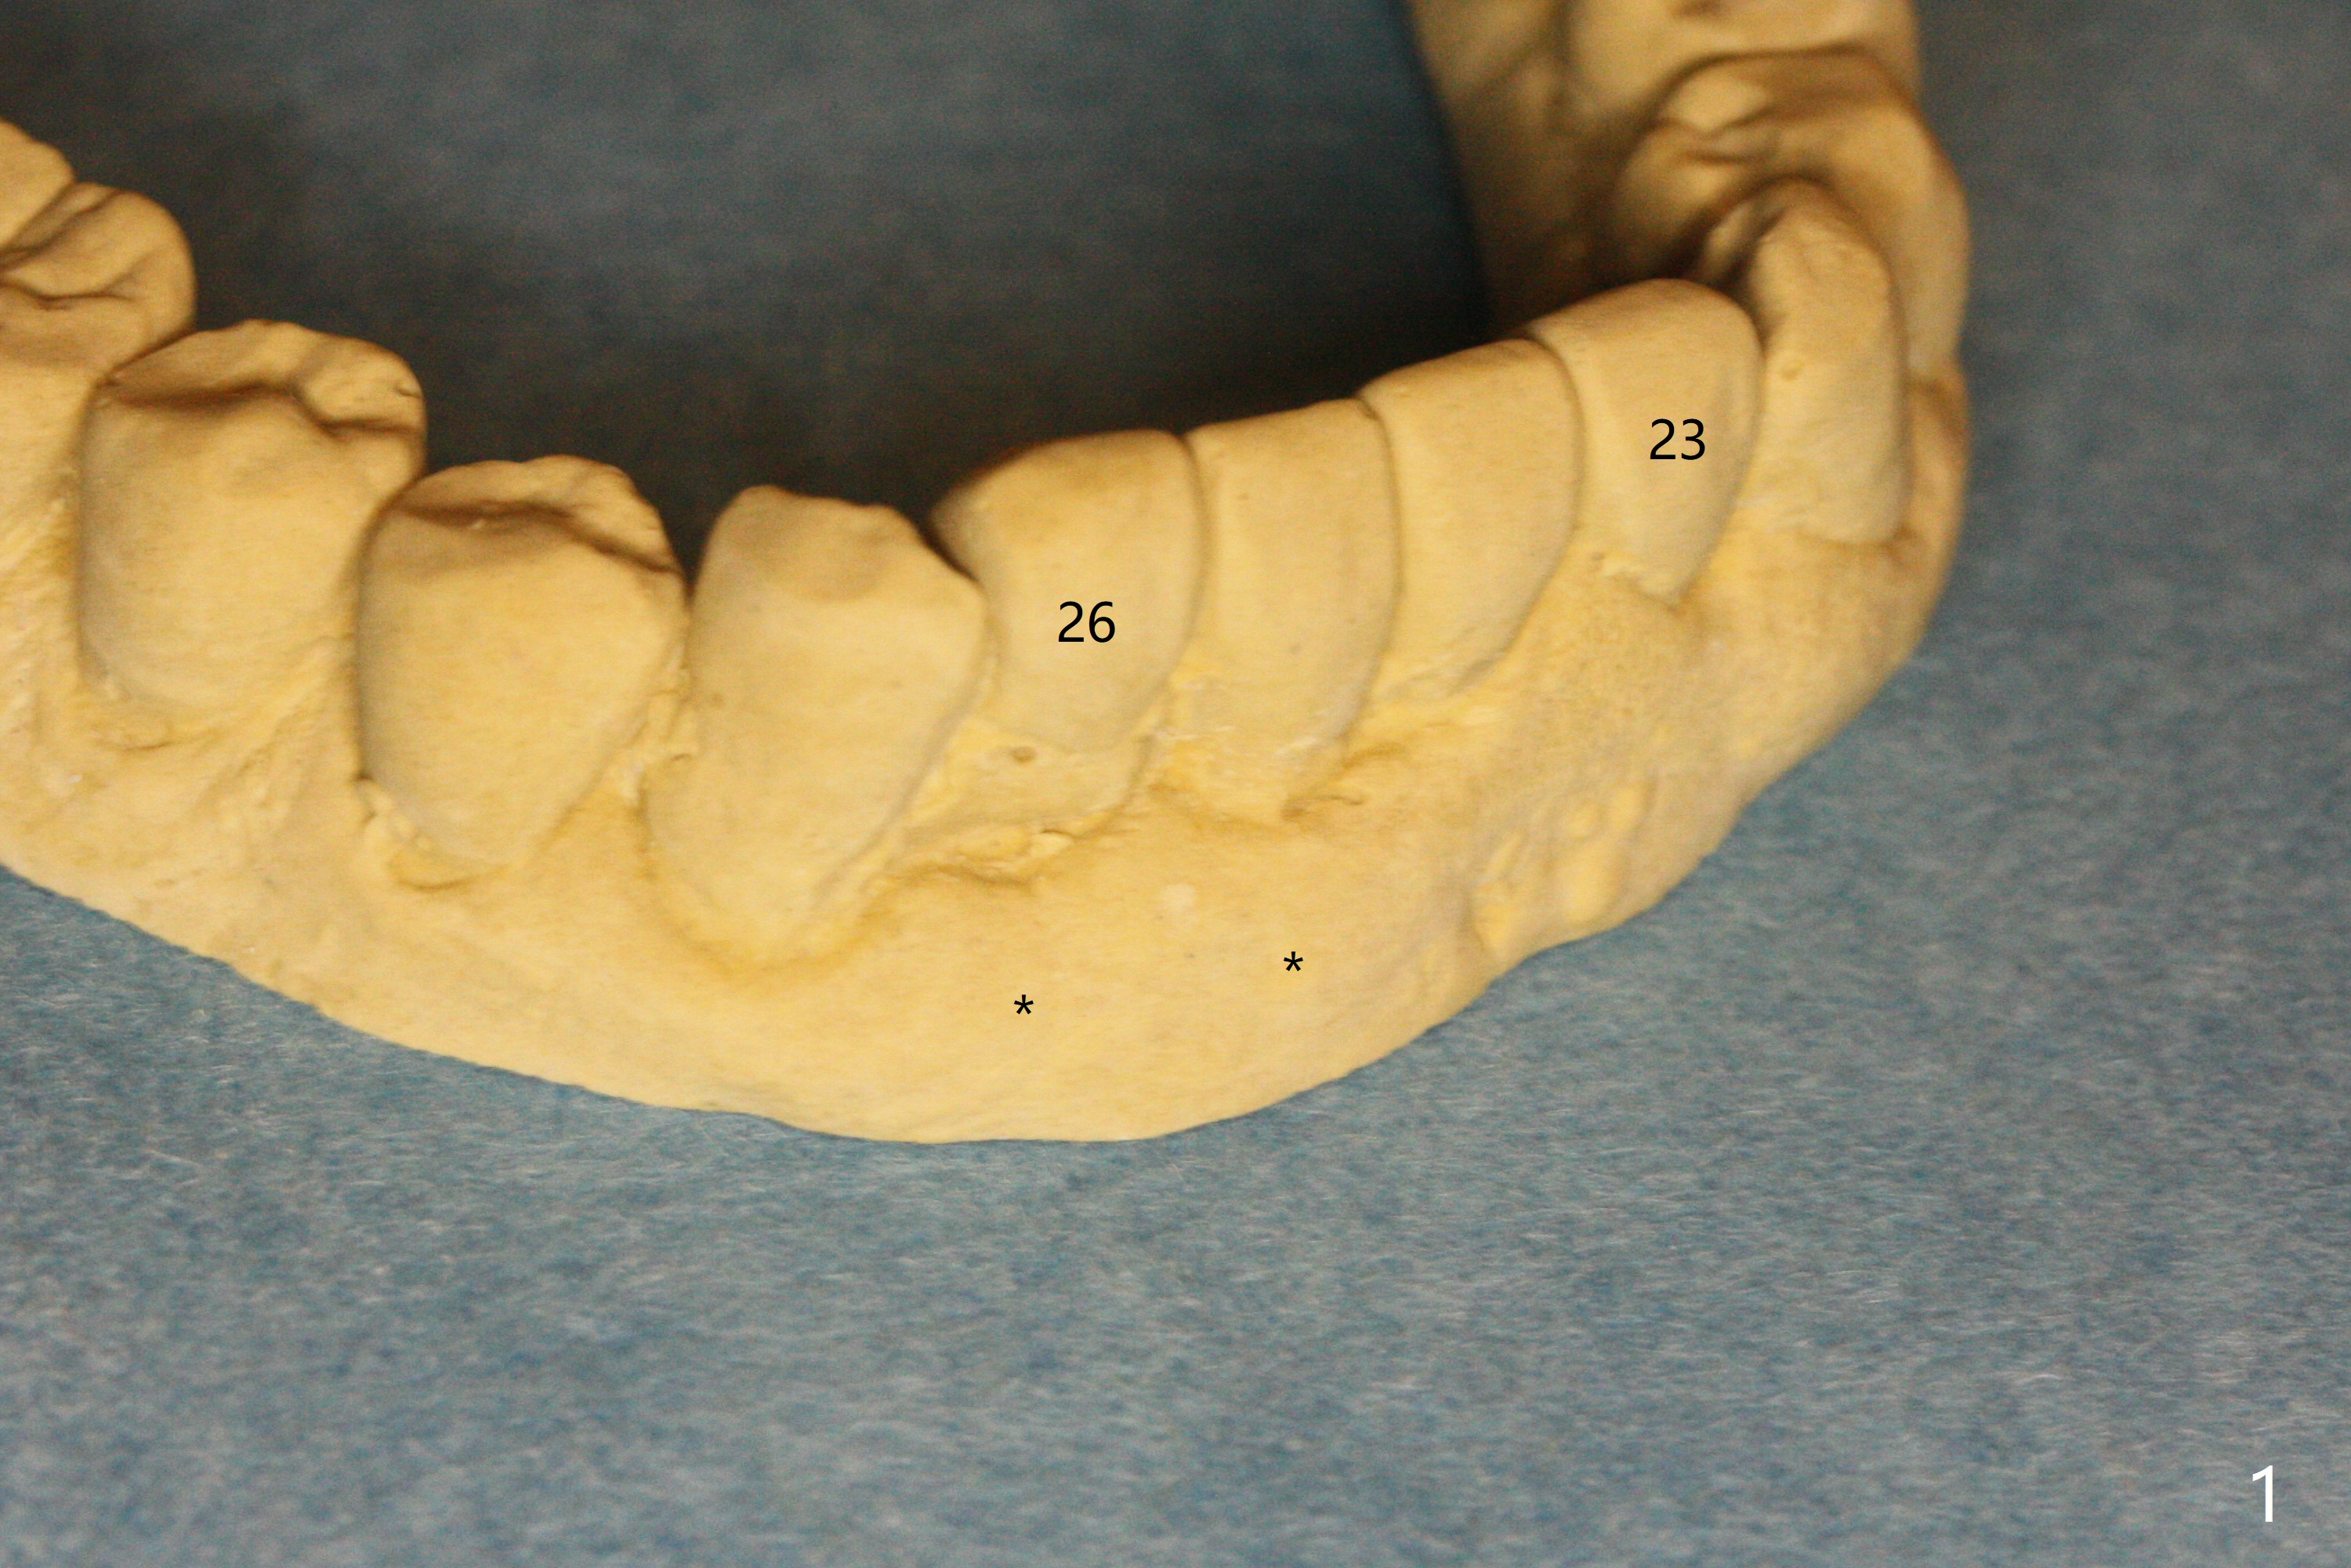

A 58-year-old man with splinted crowns at #23-26 has buccal abscess and lingual gingival recession at #25 and 26 (Fig.1,2). Large periapical radiolucency involves all of the 4 incisors (Fig.3). Note residual crestal bone between the incisors (*). It appears that a 1-piece implant with 4 mm cuff (Fig.4 pink) should be placed on the right side, while a longer 1-piece implant (23 mm) with shorter cuff (1.5 mm) on the left side. A provisional FPD will be fabricated from a stent.